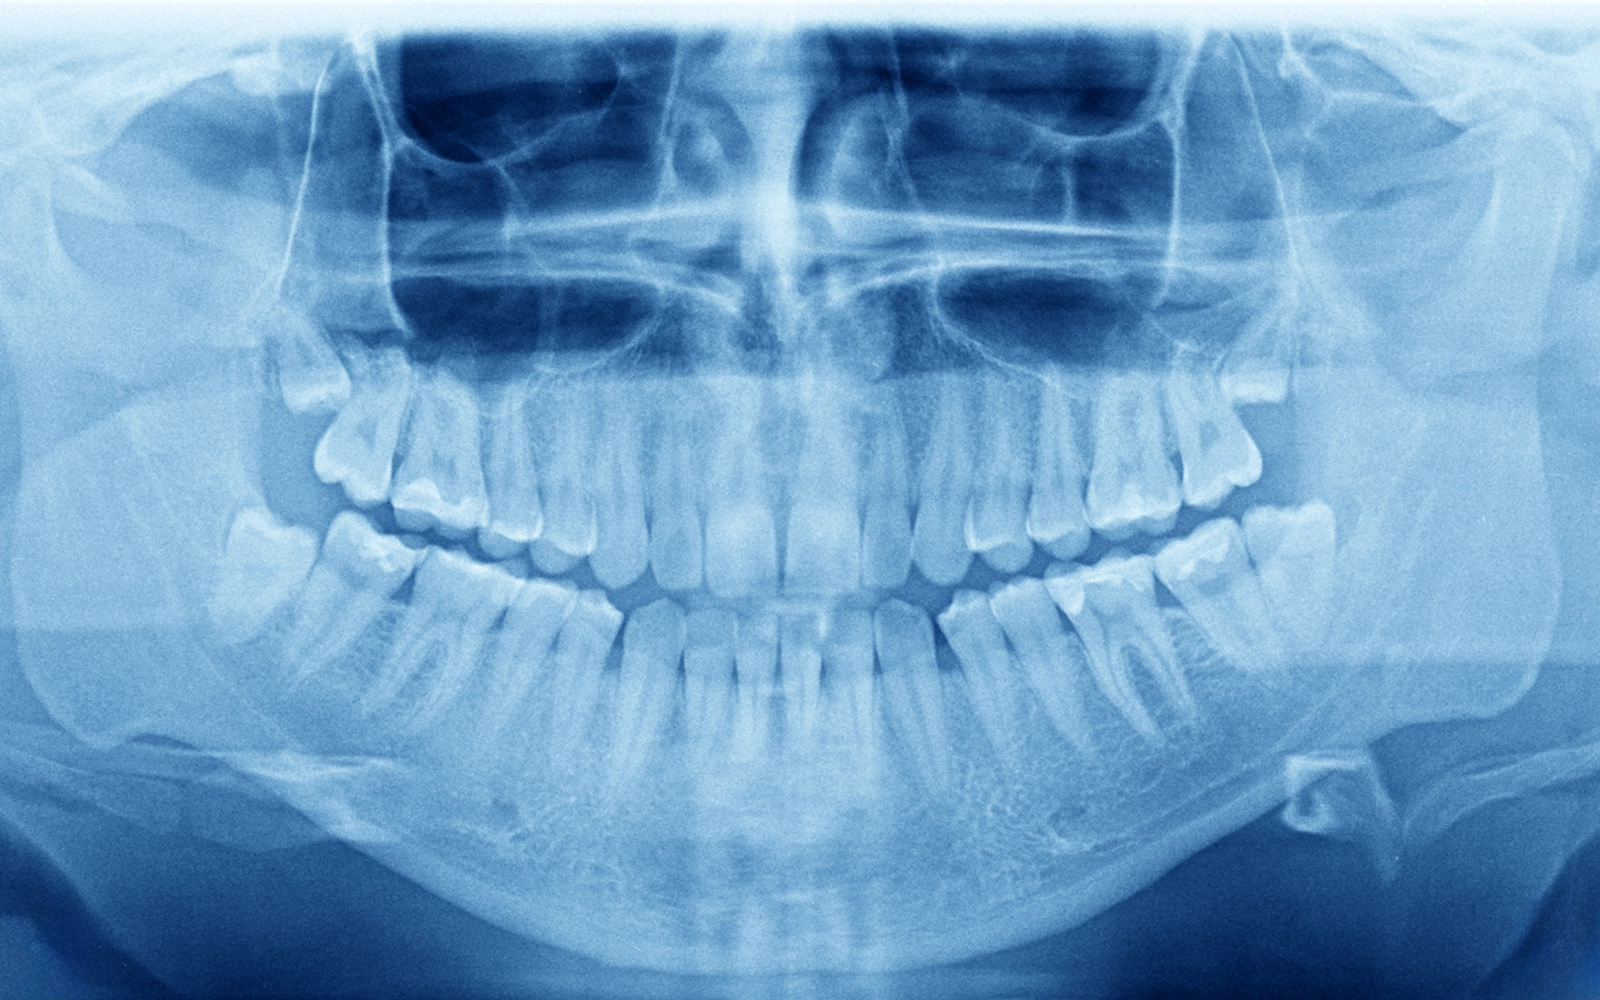

口腔外科は、お口の中やその周囲に生じる様々な疾患を、外科的な手法を用いて治療する診療科です。

一般的な歯科治療が虫歯や歯周病を中心に扱うのに対し、口腔外科では親知らずの抜歯、顎の骨や粘膜にできる腫瘍、外傷、顎関節症など、より幅広い疾患に対応します。口腔外科が扱う主な疾患には、以下のようなものがあります。

CT撮影による詳細な診断

口腔外科治療においては、正確な診断が治療の成功を左右します。当院では、CT撮影により、病変の位置や大きさ、周囲の組織との関係を三次元的に把握します。

例えば、顎の骨の中にできる嚢胞や腫瘍の場合、CTにより病変の範囲を正確に把握し、周囲の神経や血管との位置関係を確認した上で、安全な手術計画を立てることができます。

また、顎関節症の診断においても、CTにより関節の状態を詳しく評価します。

顎の骨の中にできる嚢胞や腫瘍は、通常は症状がなく、レントゲン検査で偶然発見されることが多いです。

放置すると徐々に大きくなり、骨を破壊してしまうため、発見された場合には早めの治療が推奨されます。

- その他の嚢胞・腫瘍顎骨嚢胞、エナメル上皮腫など、様々な病変があります。CT検査で詳細に診断し、病変の範囲に応じた摘出手術を行います。